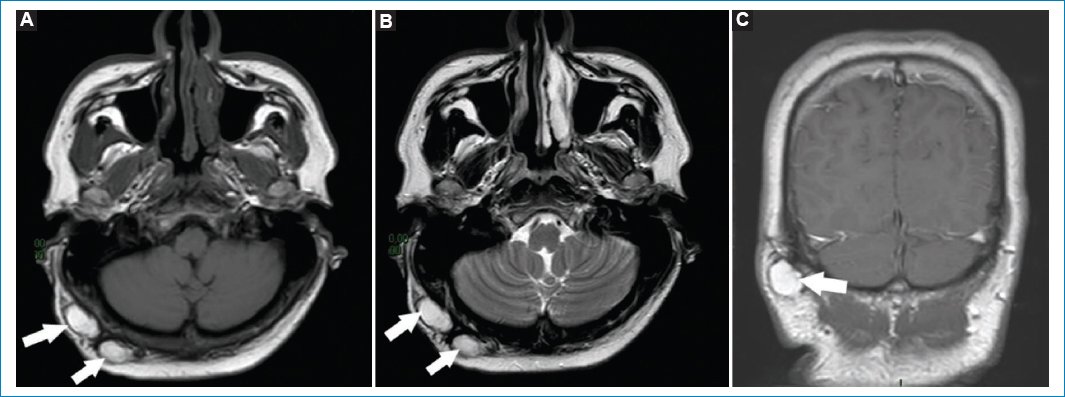

La hipertrofia adenoidea puede observarse en pacientes jóvenes o en adultos jóvenes, atópicos o roncadores. Es evidenciable en RM como una masa de tejidos blandos, con estrías y quistes de retención pequeños; es hiperintensa en T2 e isointensa e T1, disminuyendo la vía aérea parcialmente (Fig. 3)17.

Figura 3. (A y B) Cortes axiales ponderados en T2. Las flechas señalan la hipertrofia adenoidea en dos pacientes distintos. Se aprecia engrosamiento hiperintenso con microquistes asociados, obliterando parcialmente la luz de la vía aérea.